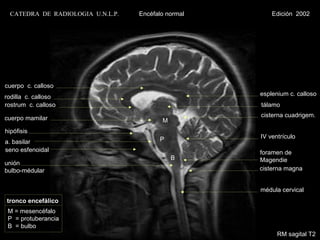

CATEDRA DE RADIOLOGIA U.N.L.P.   Encéfalo normal       Edición 2002

cuerpo c. calloso

rodilla c. calloso                                   esplenium c. calloso

rostrum c. calloso                                   tálamo

cuerpo mamilar                                       cisterna cuadrigem.

M

hipófisis

P           IV ventrículo

a. basilar

seno esfenoidal                                      foramen de

B      Magendie

unión

bulbo-médular                                        cisterna magna

médula cervical

tronco encefálico

M = mesencéfalo

P = protuberancia

B = bulbo

RM sagital T2